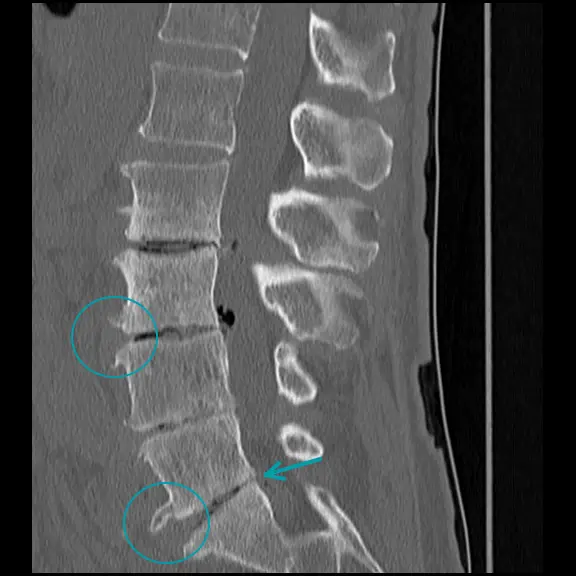

Spondylosis can be detected through spinal imaging such as X-rays, magnetic resonance imaging (MRI), and computed tomography (CT) scans. A typical X-ray report may describe osteophytes (bony growths), narrowing of intervertebral spaces, sclerosis of the vertebral endplates, facet joint degeneration, and soft tissue calcifications. The extent of degenerative changes seen on imaging does not necessarily correlate with a patient’s symptoms. Some patients with minimal changes may experience severe pain, while others with significant spondylosis may have no symptoms at all.

CT scans provide detailed imaging of bony structures and are superior to X-rays for evaluating foraminal stenosis, especially when hypertrophy of the facet or uncovertebral joints is present. CT is less effective than MRI for visualizing soft tissues and nerve structures.